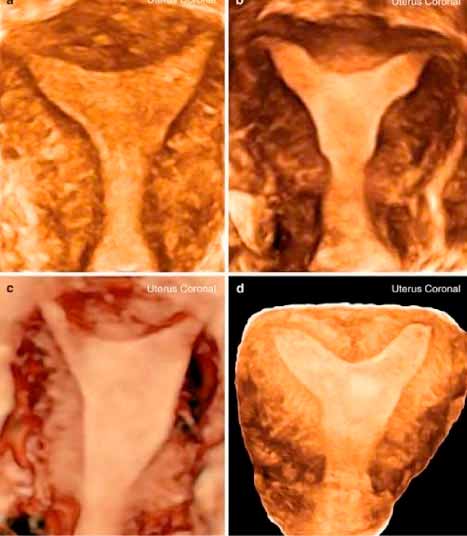

Somos expertos en detección temprana de anomalías. Brindamos una gama completa de Ultrasonidos Fetales y Ecografías 5D-7D: